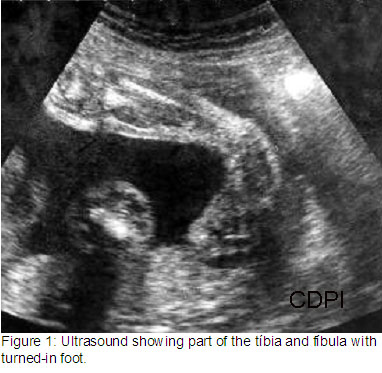

3.) Clubbed Foot

Clubbed foot is a turning of the ankle. One or both feet can be affected.

On ultrasound, clubfoot can be seen and diagnosed through evaluating the angling of the foot. Clubfoot can be either an isolated finding or syndromic. If syndromic, abnormalities such as heart defects (problems with the structure), micrognathia, and clenched fists might be present.

Clubfoot cannot be treated while in utero, but can be once the baby is delivered. Depending on the severity of the clubbing, treatment ranges from braces to surgery.